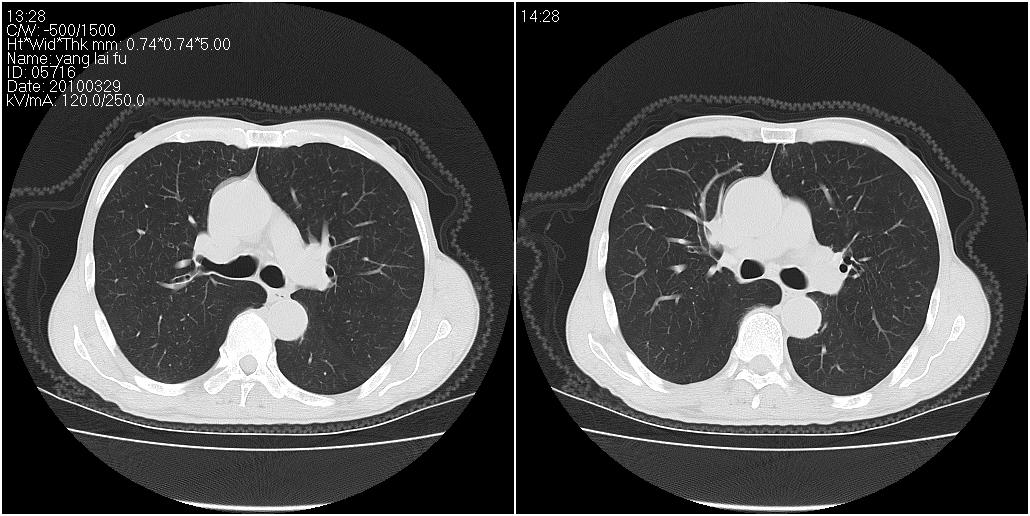

标题: ct增强:

[本贴已被 fanshl 于 2010-3-30 7:14:31 修改过]

作者: 施明 时间: 2010-3-30 16:07

炎性肿块

右肺中叶阻塞性不张及肺炎,高度怀疑支气管占位,建议纤支镜检查!